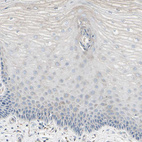

Immunohistochemistry analysis in human cerebral cortex and cervix, uterine tissues using HPA008147 antibody. Corresponding ATP6V1B2 RNA-seq data are presented for the same tissues.